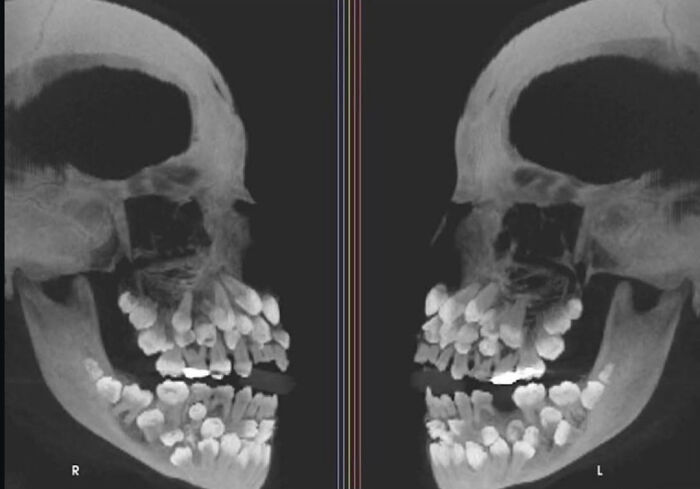

An X-Ray Of A Patient With Hyperdontia (The Condition Of Having More Teeth Than Average). Usually Adults Have 32 Teeth. This Person Had 81